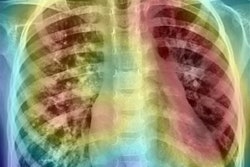

Images of a 62-year-old man with primary adenocarcinoma. Left and middle: Posteroanterior digital chest radiographs. Left: Without DCNN software assistance, three readers interpreted this image as a normal chest radiograph. Middle: According to the DCNN's suggestion (dotted circle), all readers were able to identify a true nodule (yellow circle). Right: Axial CT image obtained on the same day shows a 25-mm solid mass in the apical segment of the right upper lobe (arrow). Images courtesy of the RSNA.Furthermore, the software's detection performance on its own was similar to the average performance of radiologists for malignant lung nodules, according to the authors.